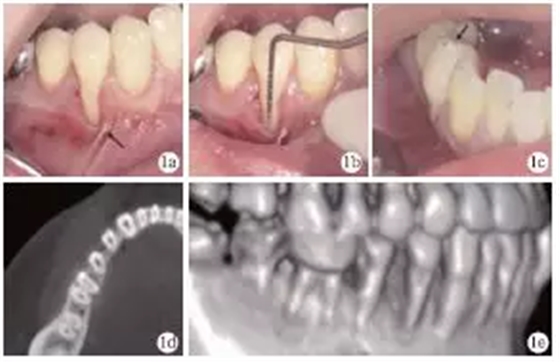

臨床檢查發(fā)現(xiàn),患者全口牙齦無(wú)明顯紅腫,探診深度1~4mm,BOP(+)<15%;#44頰側(cè)牙頸部充填物,頰側(cè)可見(jiàn)9mm齦退縮,超過(guò)膜齦聯(lián)合,僅存小于1mm的角化齦,且近中見(jiàn)系帶附著,近遠(yuǎn)中齦乳頭均存在輕度退縮(圖1a、1b);正中咬合時(shí)可捫及#44功能性動(dòng)度,頰尖舌斜面可見(jiàn)咬合高點(diǎn)(圖1c)。術(shù)前CT見(jiàn)#44頰側(cè)牙槽骨吸收達(dá)根尖1/3,鄰面擴(kuò)展達(dá)根間區(qū),鄰面牙槽骨高度降低(圖1d、1e)。根據(jù)臨床檢查和CT檢查,診斷為#44Miller Ⅲ°牙齦退縮。

圖1 術(shù)前臨床及X線檢查